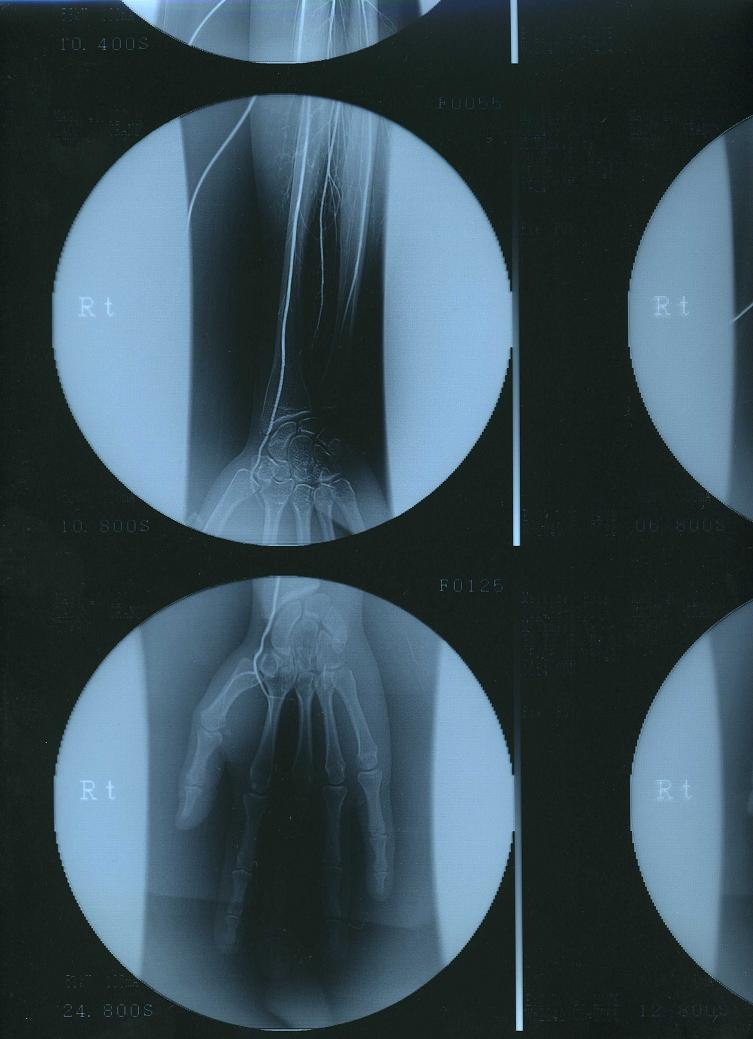

そして、初めてカミングアウトする病気は…病名『ビュルガー病』

この病気は9割方、男性がかかる病気なので、女性と老人が疑わしい時は男性より厳しい検査をします。

血液が指の先に十分に流れないので…

爪の発育がとても悪く、脆い歪な爪をしています。

本来なら強く固い親指の爪は人差し指の爪で簡単に削ったり、破ったりできます。